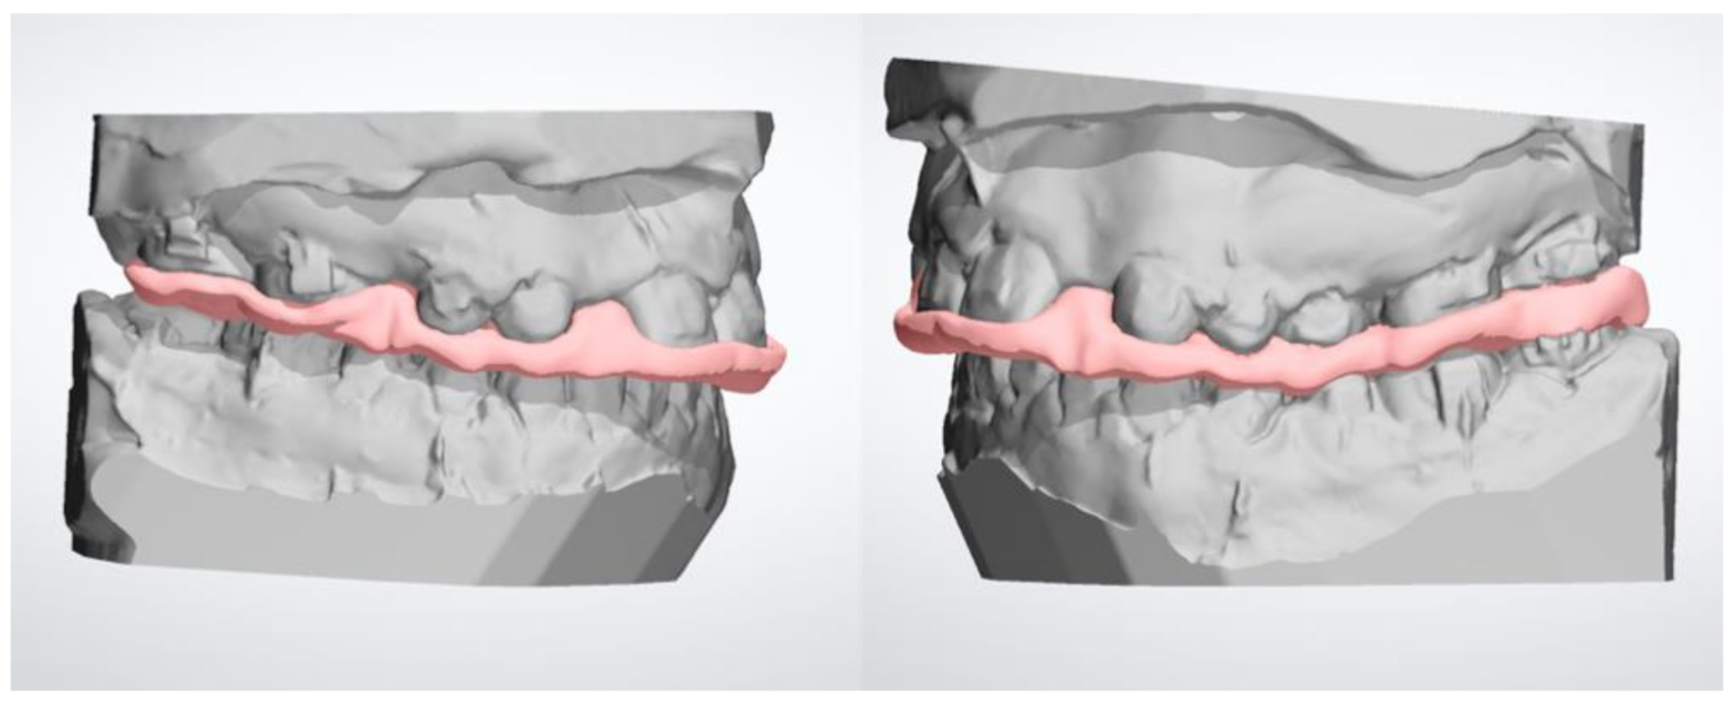

2. Materials and Methods

3. Results